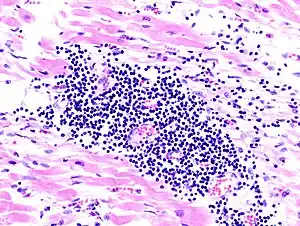

![]() O imagine la microscop a miocarditei la autopsie la o persoană cu debut acut de insuficiență cardiacă | |